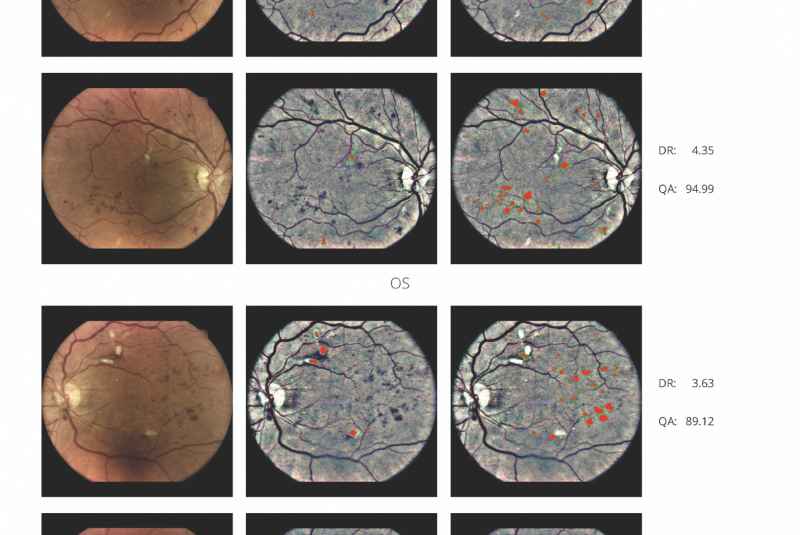

AI (umělá inteligence) okamžitě rozpozná příznaky diabetické retinopatie a klasifikuje výsledky podle závažnosti na základě mezinárodní klasifikace. Získáte přehled s hodnocením závažnosti zachycení, kdy se po analýze snímků pořízených kamerou iCare DRSplus automaticky vygeneruje zpráva pro pacienta se stupnicí závažnosti diabetické retinopatie na základě mezinárodních standardů (ICDR, AREDS).

Fundus kamera iCare DRSplus pořídí celkem 4 vysoce kvalitní snímky TrueColor (dva z pravého a dva z levého oka), které se automaticky uloží do cloudu a odešlou ke zpracování umělé inteligenci - AI. Zpráva je k dispozici okamžitě a může být zkontrolována s pacientem během téže návštěvy lékaře.

- Výsledek na škále 0-4 podle ICDR

- International Clinical Diabetic Retinopathy

(medzinárodní klinická škála závažnosti diabetické retinopatie) - Výsledek generovaný na základě 2 snímků z každého oka

(centrální a nazální)

Medzinárodní oftalmologický standard vyžaduje

výsledek podla min. 2 snímků z každého oka.